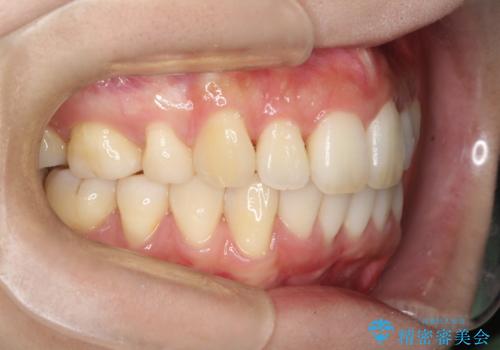

裏側装置で出っ歯の矯正治療

裏側からの矯正であったため、表側に比べて少し治療期間を要しました。

目立たずに矯正治療を終えることができ、満足していただけました。